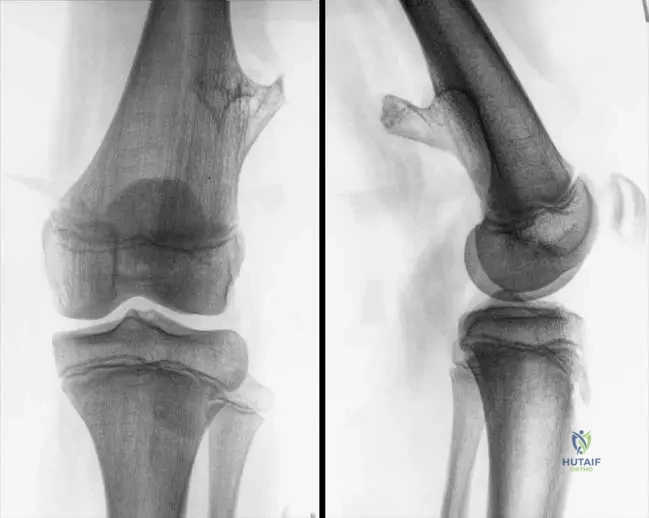

A 14-year-old male presents with a slowly growing, painless mass on the distal femur. Physical examination reveals a firm, non-tender, fixed bony prominence. Radiographs show a bony projection arising from the metaphysis of the distal femur, with clear continuity of the cortex and medullary bone between the lesion and the parent bone.

Rationale: The clinical presentation of a slowly growing, painless bony mass in an adolescent, combined with radiographic findings of cortical and medullary continuity with the parent bone, is pathognomonic for an osteochondroma. Enchondromas are intramedullary lesions, fibrous dysplasia has a characteristic ground-glass appearance, non-ossifying fibromas are typically cortical defects, and osteoid osteomas present with nocturnal pain relieved by NSAIDs and a nidus on imaging.

A 10-year-old girl is evaluated for a palpable mass near her knee. Radiographs demonstrate a bony exostosis originating from the lateral aspect of the proximal tibia. The most critical radiographic feature to confirm the diagnosis of an osteochondroma is:

Rationale: The radiographic hallmark of an osteochondroma is the demonstration of cortical and medullary continuity between the lesion and the parent bone. This feature distinguishes it from other bony exostoses or surface lesions. A sclerotic margin is non-specific, a lucent nidus is characteristic of an osteoid osteoma, periosteal reaction suggests inflammation or aggressive process, and soft tissue calcification is not a primary diagnostic feature of osteochondroma itself.

A 10-year-old boy presents with a palpable mass on the distal femur. Radiographs confirm an osteochondroma. Based on typical growth patterns, in which direction would this lesion most likely grow?

Rationale: The clinical context for Fig. 8.31 a, b states, "Lesions typically grow away from the joint." This is a characteristic growth pattern of osteochondromas. The main distractor, "Towards the joint space," is incorrect as this is contrary to the typical growth pattern.